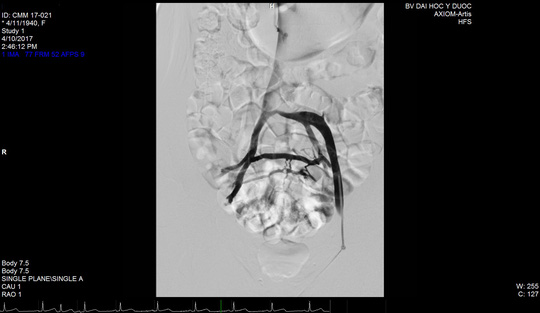

Tĩnh mạch người bệnh bị tắc trứơc khi đặt stent.